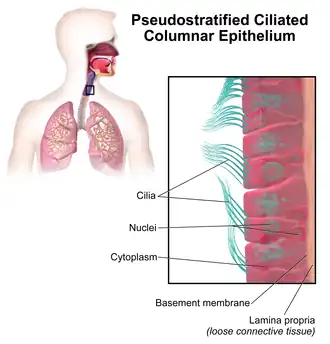

Pseudostratified columnar epithelium

Illustration depicting ciliated pseudostratified columnar epithelium. | |

Pseudostratified columnar epithelium is a type of epithelium that, though comprising only a single layer of cells, has its cell nuclei positioned in a manner suggestive of stratified columnar epithelium. A stratified epithelium rarely occurs as squamous or cuboidal.

The term pseudostratified is derived from the appearance of this epithelium in the section which conveys the erroneous (pseudo means almost or approaching) impression that there is more than one layer of cells, when in fact this is a true simple epithelium since all the cells rest on the basement membrane. The nuclei of these cells, however, are disposed at different levels, thus creating the illusion of cellular stratification. All cells are not of equal size and not all cells extend to the luminal/apical surface; such cells are capable of cell division providing replacements for cells lost or damaged.

Pseudostratified epithelia function in secretion or absorption. If a specimen looks stratified but has cilia, then it is a pseudostratified ciliated epithelium, since stratified epithelia do not have cilia. Ciliated epithelia are more common and lines the trachea, bronchi. Non-ciliated epithelia lines the larger ducts such as the ducts of parotid glands.